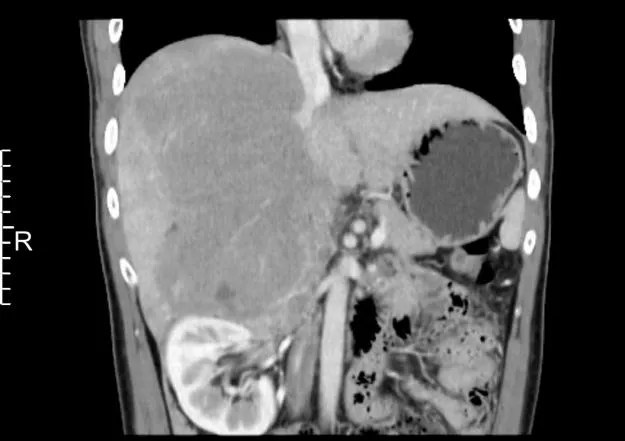

近日,河北医科大学第二医院普外一科在多学科团队的紧密协作下,成功为一名患者精准切除18公分巨大腹膜后肿瘤。这一高难度手术展现了医院在复杂手术领域的精湛技艺和雄厚实力,彰显了我院多学科医护团队面对复杂病情...